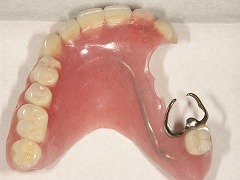

他院で入れ歯を製作したが、いれていられない患者さん。

初診時 |  初診時 |  初診時 | |

年齢層 | 60代 男性 |

どんなお悩み | 他院で入れ歯を製作したが痛くて、いれていられない患者さん。 残っているかぶせ物を外して、残ってる歯に二重に冠をかぶせて入れ歯をとめる義歯を制作(コーヌスデンチャー) |

治療期間 | 治療期間は4か月程度 |